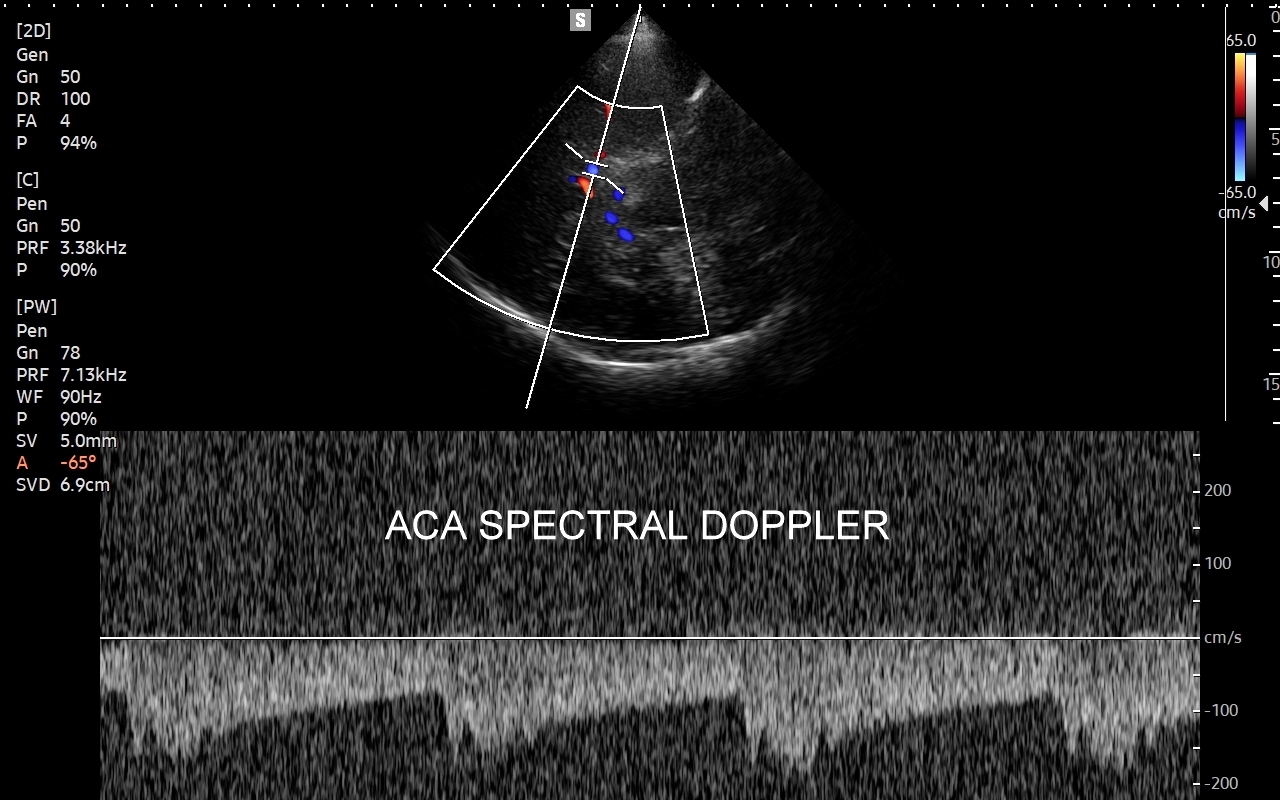

Badanie USG Doppler tętnic wewnątrzczaszkowych (ang. TCCD, transcranial color-coded Doppler), nazywane także Dopplerem przezczaszkowym jest naturalnym rozszerzeniem i uzupełnieniem badania dopplerowskiego tętnic dogłowowych zewnątrzczaszkowych. Badanie polega na obrazowaniu przy użyciu dedykowanej sondy poprzez tzw. okno skroniowe czaszki głównych naczyń tętniczych mózgu, tj. koła Willisa, tętnic mózgowych przednich, środkowych i tylnych po obu stronach. Badanie TCCD umożliwia wykrycie wybranych wewnątrzczaszkowych patologii naczyniowych takich jak tętniaki, malformacje naczyniowe, zwężenia i niedrożności poszczególnych tętnic mózgowych, spazm naczyniowy, a także pozwala na ocenę kierunku przepływy krwi w kole Willisa mózgu, co  jest przydatne przy diagnostyce zespołu podkradania lub w ocenie po przebyciu udaru mózgowego.